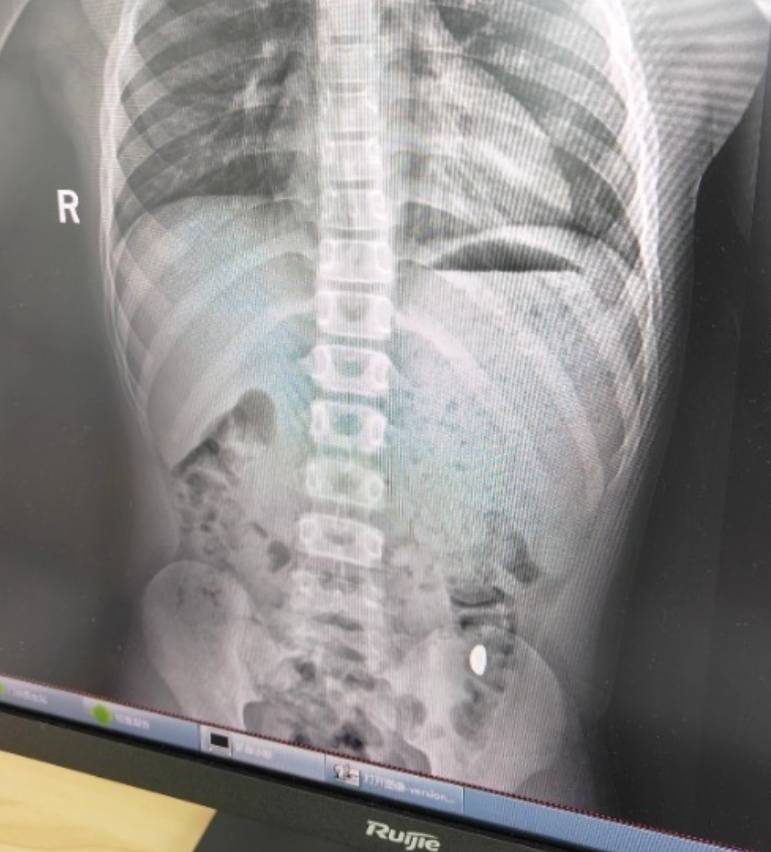

右下加亮点为金豆数字货币价格。